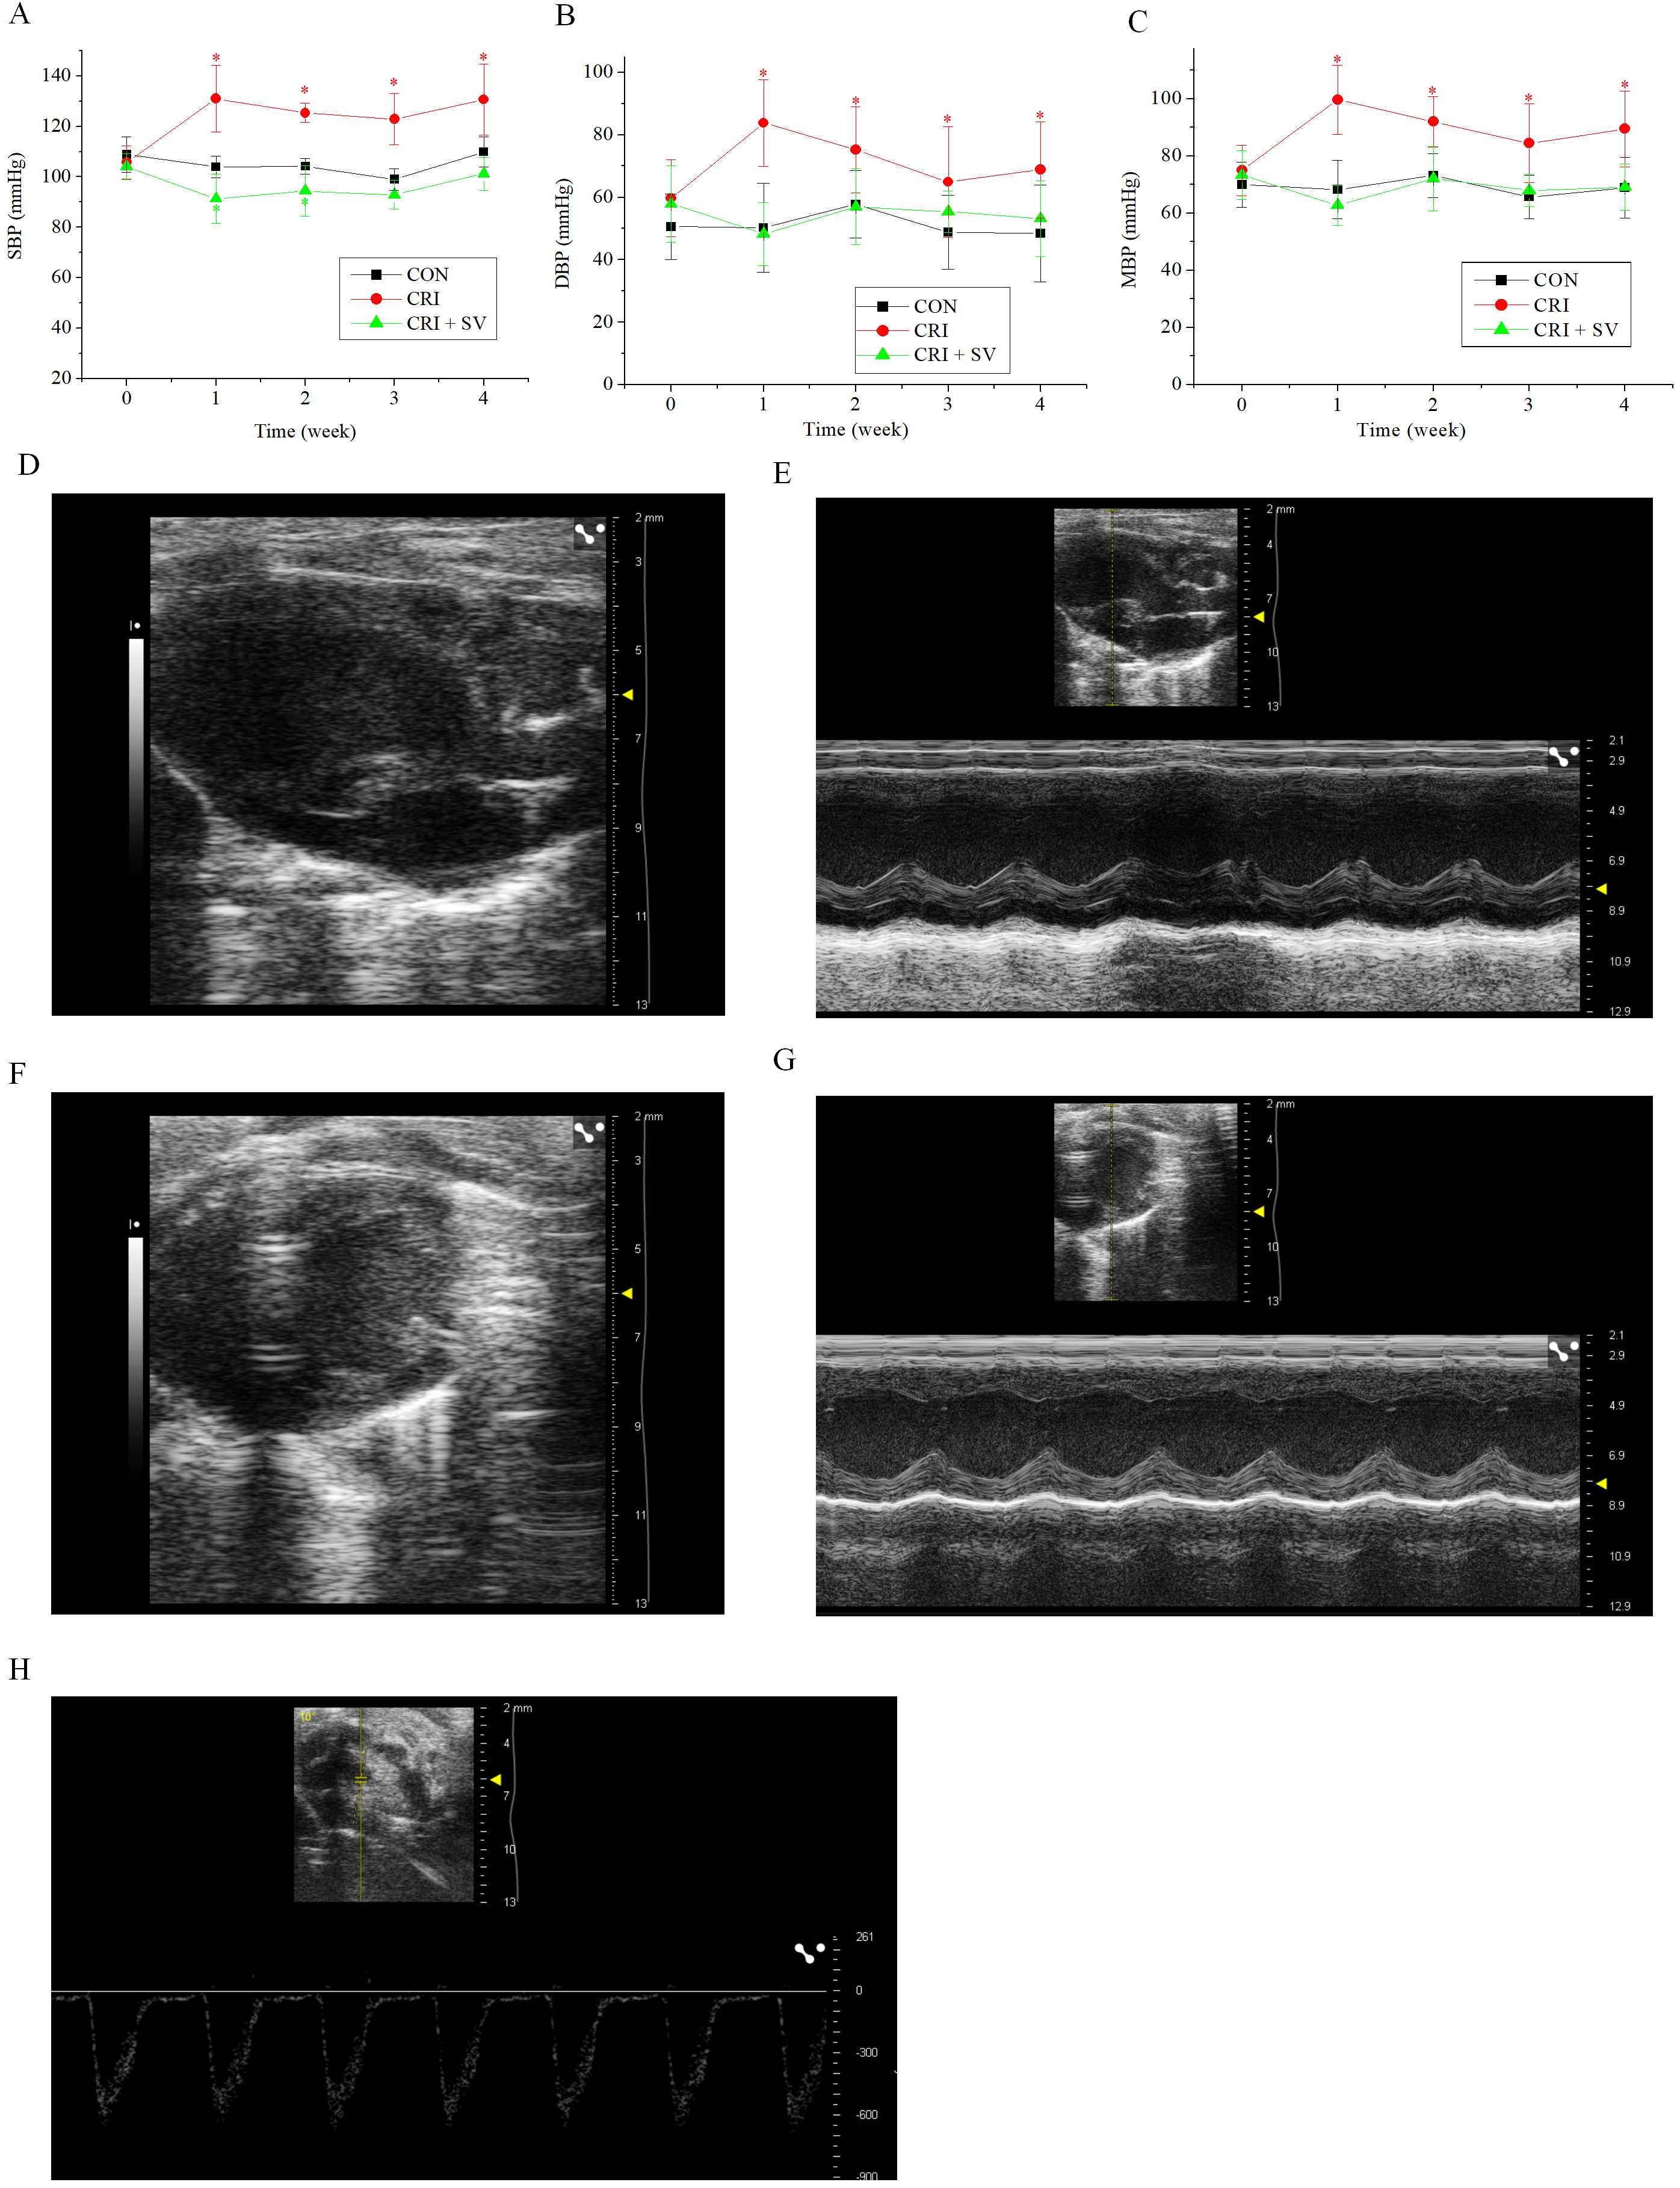

In view of the above results, crizotinib cardiotoxicity appears to be principally manifested as an increase in BP. Sacubitril/valsartan is a commonly used drug for BP reduction, thus we added an additional animal group to our study composed of crizotinib combined with sacubitril/valsartan, this was termed the crizotinib + sacubitril/valsartan group. The SBP, DBP and MBP line charts of the three experimental groups are shown in Fig. 4A–C. It can be seen that that the rise of SBP, DBP and MBP was caused by crizotinib at different timepoints (n = 10). However, data gathered indicate that sacubitril/valsartan given in combination with crizotinib can reduce elevated BP at 4 weeks when compared with the control group, SBP, p = 0.054; DBP, p = 0.473; MBP, p = 0.967.

To observe the effect of the crizotinib + sacubitril/valsartan combination on cardiac function we recorded the echocardiography of control, crizotinib, and crizotinib + sacubitril/valsartan groups. Fig. 4D–H shows typical images of the parasternal LV long-axis view. Also shown are B-type and M-type echocardiograms of long and short-axis views, and doppler pulse wave of pulmonary valve flow. Echocardiographic parameters of these three groups are shown in Table 3. The results indicated that there was no significant difference in IVSd, LVPWs, LVPWd, LVIDs, LVIDd, LVAWs, LVAWd, FS, EF or LAD among the three groups (n = 10). However, we found that the PAT of crizotinib group increased and the IVSs decreased when compared with the control group (n = 10). However, these two values returned to the level of the control group after crizotinib was combined with sacubitril/valsartan (n = 10).

Fig. 4.Effect of crizotinib and sacubitril/valsartan on BP and cardiac

function in control, crizotinib, and crizotinib + sacubitril/valsartan mouse

groups. (A) Effects of crizotinib and sacubitril/valsartan on SBP. (B) Effects

of crizotinib and sacubitril/valsartan on DBP. (C) Effects of crizotinib and

sacubitril/valsartan on MBP. (D,E) B- and M-type echocardiogram long-axis

view of the parasternal LV. (F,G) B- and M-type echocardiogram short-axis

view. (H) Doppler pulse wave of pulmonary valve flow. *p